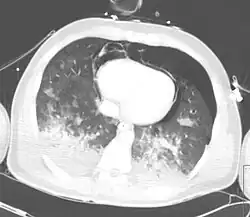

X-ray

Chest X-ray is the most common method used for diagnosis,[42] and may be used to confirm a diagnosis already made using clinical signs.[23] Consolidated areas appear white on an X-ray film.[47] Contusion is not typically restricted by the anatomical boundaries of the lobes or segments of the lung.[31][48][49] The X-ray appearance of pulmonary contusion is similar to that of aspiration,[36] and the presence of hemothorax or pneumothorax may obscure the contusion on a radiograph.[29] Signs of contusion that progress after 48 hours post-injury are likely to be actually due to aspiration, pneumonia, or ARDS.[13]

Although chest radiography is an important part of the diagnosis, it is often not sensitive enough to detect the condition early after the injury.[40] In a third of cases, pulmonary contusion is not visible on the first chest radiograph performed.[10] It takes an average of six hours for the characteristic white regions to show up on a chest X-ray, and the contusion may not become apparent for 48 hours.[10][31][48] When a pulmonary contusion is apparent in an X-ray, it suggests that the trauma to the chest was severe and that a CT scan might reveal other injuries that were missed with X-ray.[2]